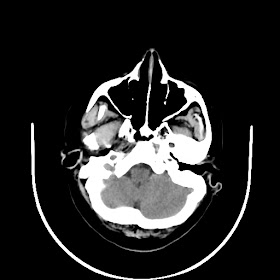

Radiological images: